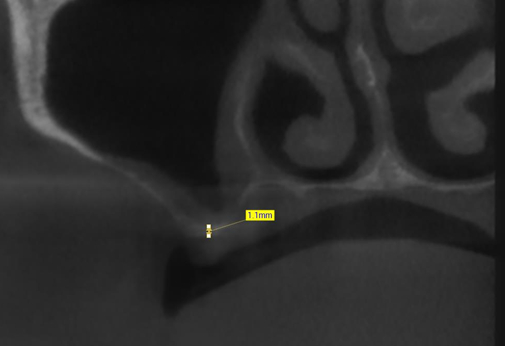

Кстати, рентген только шеи сделали. Голову не стали проверять, хотя он упал прямо на неё и мы об этом говорили, да и по его лицу это было видно.

Посмотрел снимки только. Сказал, что, скорее всего, ушиб. А точнее - потом будут узнавать.